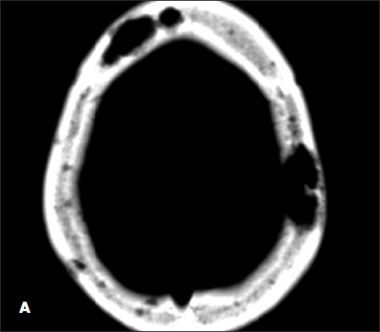

The patient had mild leukocytosis, anemia, and corrected calcium level of 11 mg/dL. Cerebrospinal fluid analysis yielded normal results. A brain CT scan showed multiple lytic lesions in the calvarium, with the largest in the left parietal bone (A). Abdominal CT revealed hepatosplenomegaly with low-attenuation lesions and scattered lucencies throughout the vertebral bodies (B).

Kaposi sarcoma or Mycobacterium haemophilum infection can lead to lytic lesions in bones.5,6 However, MAIC infection as a cause of lytic bone lesions has not been described. Further studies are needed to verify whether lytic lesions explain hypercalcemia in disseminated MAIC infection in persons with HIV/AIDS in the absence of elevated vitamin D levels.